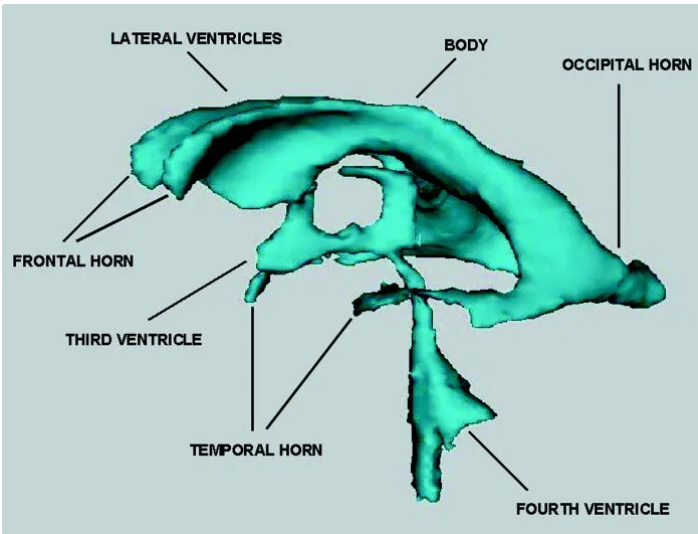

The purple hippocampus is visualized tracing the ventricular system (turquoise).